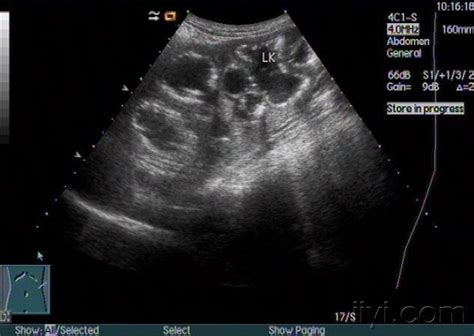

24周 四维彩超胎儿双肾肾盂分离

胎儿双肾集合系统分离就是肾积水,由输尿管,尿道的狭窄造成,胎儿双肾都会有一些积水,如果宽度在1.0cm以下,以后复查不继续增长,就没有问题。宽度超过1.5cm,一般都有问题,1.0-1.5cm则可疑有事,须密切的观察,如继续增长,就有事啦。

当胎儿憋尿时,可以发生双肾盂分离。不放心最好间隔复查,b超复查后可能消失。如果继续增大,应考为肾脏发育问题。

您好:正常胎儿肾脏的集合系统可有轻度分离,分离径可达6毫米,一般不超10毫米,均不能诊断为肾积水,孕期对于胎儿泌尿系统的检查较为局限,目前来说,您的胎儿肾盂增宽,现在还不能确定此肾盂积水对胎儿生后是否会造成影响及何种影响。有些轻度肾盂增宽的胎儿生后随访复查中,可逐渐消失,且对孩子的正常生活及生长发育没有不良影响,建议您继续复查。